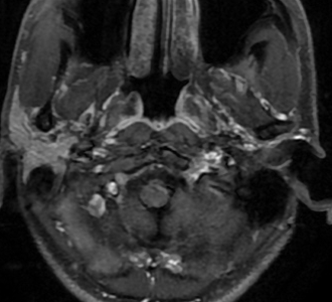

术前影像

入院后行术前检查,核磁共振显示:斜坡偏左占位,脑膜瘤可能性大。

左侧斜坡脑膜瘤